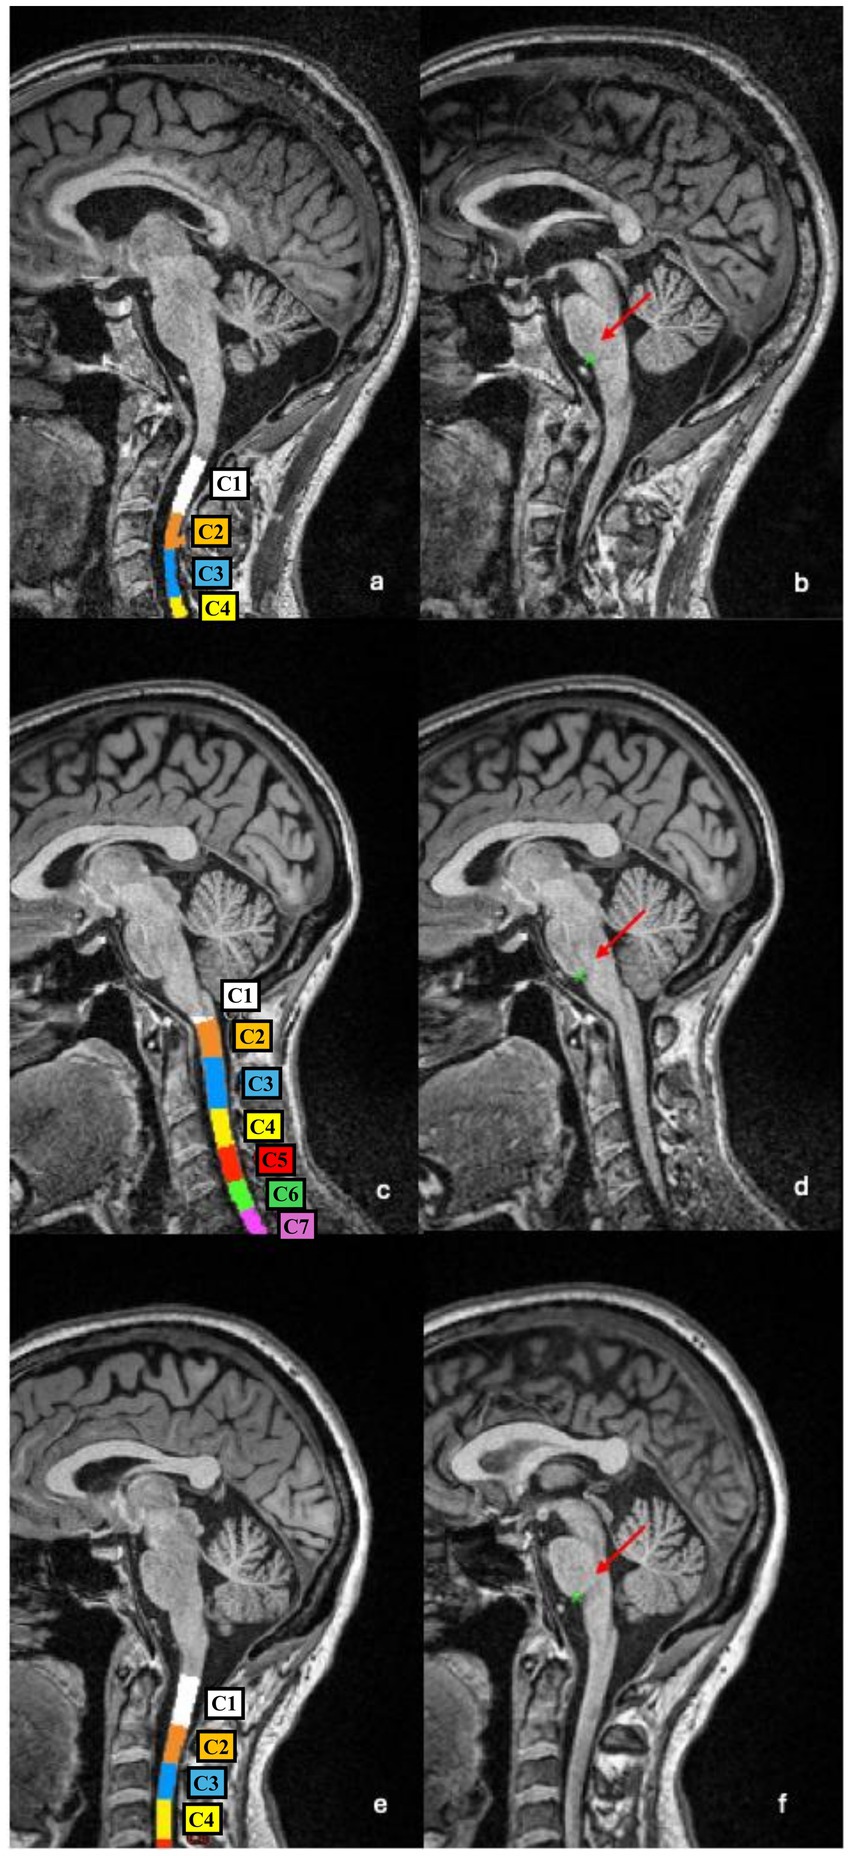

Despite the observed strong correlation, some notable discrepancies emerged in a subset of patients. Upon visual inspection of the segmentations and vertebral labelling, we identified that the PMJ was consistently and accurately detected across all subjects (75/75, 100%), while the vertebral labelling algorithm misidentified the C2–C3 disc level in 24/75 (32%) subjects. Figure 2 shows examples of vertebral labelling that are, respectively, incorrect, partially inaccurate, and anatomically correct at the C2–C3 level, and how this affected CSA C2–C3 measures. In contrast, the PMJ was accurately and automatically identified in all patients.

Figure 2

Six-panel MRI images of the cervical spine and brain. Panels a, c, and e highlight color-coded cervical segments. Panels b, d, and f show red arrows pointing to the pontomedullary junction (PMJ). Each panel documents different levels of spinal and brain anatomy.

Figure 2. Examples of vertebral segmentation and labelling errors. (a,b) In this patient the C1–C2 complex and C3 vertebras were incorrectly labelled as C1 and C2, respectively, resulting in a downward shift of all subsequent levels (a). As a consequence, the CSA measured at the (misidentified) C2–C3 level is underestimated (43.32 mm2 vs. 55.99 mm2 if vertebral labelling is manually corrected). The PMJ-referenced segmentation method correctly detects the PMJ (b), and the CSA measured at 64 mm caudal to the PMJ is more anatomically accurate (57.09 mm2). (c,d) In this patient, part of the C2 vertebral body was incorrectly labelled as C3 (c), leading to an overestimation of CSA (77.46 mm2 vs. 71.68 mm2 if vertebral labelling is manually corrected). The PMJ identification is accurate (d), and the CSA measured 64 mm caudal to the PMJ appears more reliable (72.56 mm2). (e,f) In this patient, the vertebral labelling is anatomically correct (e) as well as the identification of the PMJ (f). CSA C2–C3 and CSA PMJ measures are therefore more comparable (55.33 mm2 and 55.05 mm2, respectively).